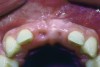

The patient's endodontic examination revealed a flexible splint from teeth Nos. 7 through 10 (Figure 1). Tooth No. 8 had a 3 mm x 3 mm class II fracture of the mesioincisal portion of the crown. Tooth No. 9 had a class IV fracture of the crown running labiopalatally from the remaining 2 mm of the crown to bone level on the palatal. A pulpotomy had been performed on the exposed pulp. Both teeth exhibited class III mobility. Teeth Nos. 7 through 10 did not respond to cold testing. None of the teeth were tender to palpation, and only tooth No. 9 had a slight positive response to percussion. Periodontal probings of tooth No. 8 were 4 mm to 5 mm on both the labial and palatal aspects. There was a narrow 12 mm probing on the straight palatal of No. 9; the remaining probing depths were 4 mm to 5 mm.2 A periapical radiograph showed both teeth Nos. 8 and 9 to have incompletely formed roots with wide-open foramina (Figure 2).

Fig 2. Age 8. Radiograph of teeth Nos. 8 and 9 at initial examination.

Figure 2